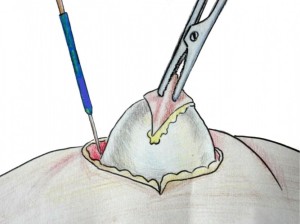

Процедура удаления жировика требует тщательной разработки плана лечения. При этом учитывается размер, локализация, плотность жировых тканей и общее состояние пациента. Главным требованием при удалении жировика является сокращение вероятности рецидива и осложнений течения заболевания. Поэтому удаление жировика всегда трудоемкий процесс, который требует от врача хирурга большой профессиональной практики и квалификации.

Среди консервативных методов удаления жировика стоит выделить один из методов. А именно метод удаления жировики с помощью специальных медикаментов введенных в полость жировика. Данный метод применяется для удаления небольших жировиков до двух сантиметров в диаметре. С помощью специальной иглы в ткань жировика вводиться специальная жидкость и по истечению несколько месяцев жировик полностью рассасывается. Данный метод должен проводиться опытным врачом хирургом в клинических условиях.

Существуют также аппаратные и хирургические методы удаления жировика. Такие методы применяются для удаления жировика в короткий период с максимальным терапевтическим результатом. Такие методы имеют некоторые противопоказания и их использование должно обговариваться с лечащим врачом.

• Хирургическое иссечение.